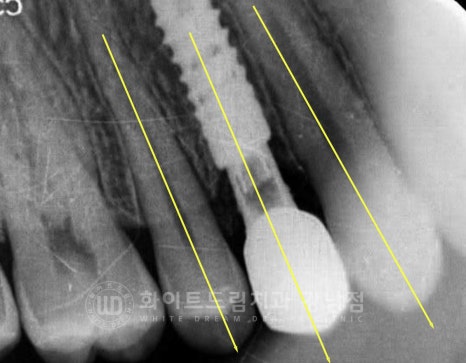

이렇게 인접치 사이에 임플란트를 식립할 때는

주위 인접치와 평행선을 이루도록 식립 방향(path)를 잘 잡고 진행해야 합니다.

그래야 치료 후 보철을 세팅할 때 더 편하고

환자분이 실제 임플란트를 사용하여 음식을 드실 때도 교합력을 유리한 쪽으로

받기 때문에 임플란트도 더 오래 사용하실 수 있답니다.